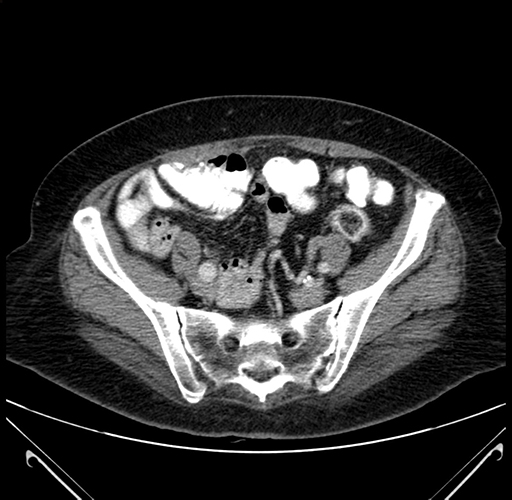

Pre-Chemo: Axial Venous

Axial Venous